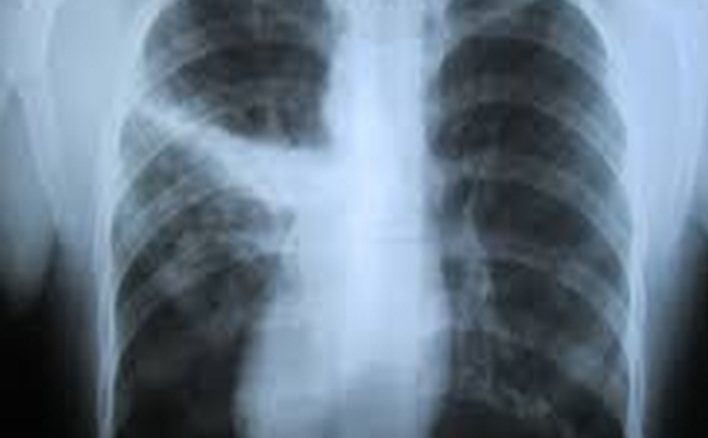

Atelektazi

“Atelektazi” akciğerin tamamının ya da bir bölümüne havanın gitmemesi nedeniyle sönmesidir. Akciğerin ilgili bölümü foksiyon göremez. Atelektazi hava yollarında mukus tıkacı, sekresyon ve balgam birikmesi, hava yoluna kaçan yabancı cisim veya hava yolunu tıkayan tümörlere bağlı gelişebilir. Ayrıca zatürre, göğüs kafesinde sıvı birikimi, akciğer zarı hastalıklarına bağlı da olabilir.

Atelektazide etkilenen akciğer alanının büyüklüğüne göre nefes darlığı ve solunum güçlüğü oluşabilir. Atelektazi vakalarının bir bölümü tedaviye gerek duymadan iyileşirken, göğüs fizyoterapisi, drenaj, bronkoskopi gibi yöntemler ile tedavi edilemeyen ileri vakalarda cerrahi tedaviye ihtiyaç duyulabilmektedir.